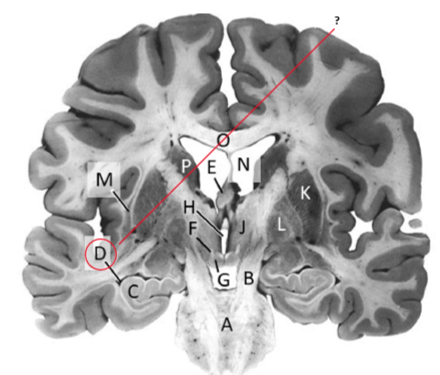

Name this and state its function.

Corpus Callosum.

Name and state its function.

Lateral ventricles.

Hippocampus.

Thalamus.

Third ventricle.

Caudate nucleus.

Name this ,state its function and the name of the structures closely associated with it.

Putamen.

Name this, state its function and its components[4 marks].

Globus Pallidus.

Components:

Crus Cerebri.

Name this and state its function. Also, state all 3 fibres involved.

Basilar pons.

Claustrum.

Name.

Temporal horn of lateral ventricle.

Name this, state its function and consequence of lesion in this area.

Fornix.

Transmits Theta waves aswell.

Lesion: anterograde amnesia.

Name this and state its function. And what tract is involved?

Mamillary bodies.